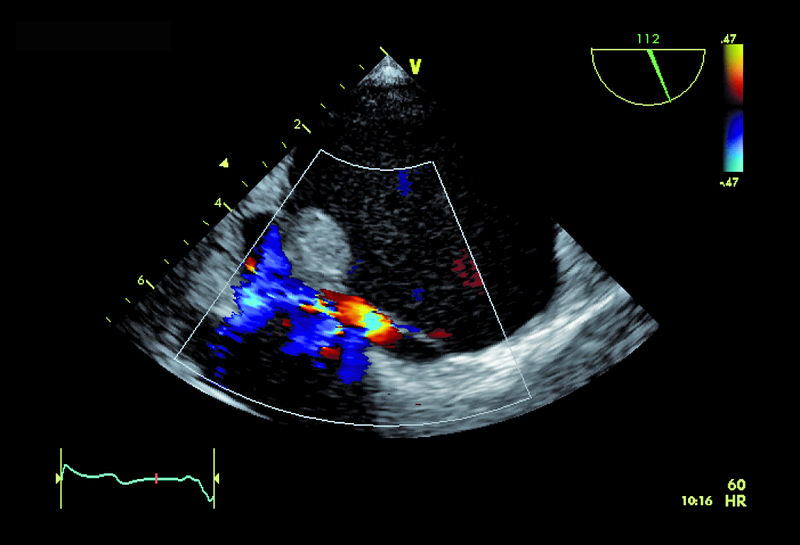

Kobieta, lat 55. Jakie patologie można rozpoznać na zamieszczonych rycinach?

1. Guz przegrody międzyprzedsionkowej (ryc. 1-3).

2. Mały ubytek przegrody międzyprzedsionkowej z przeciekiem lewo-prawym (ryc. 1-3).